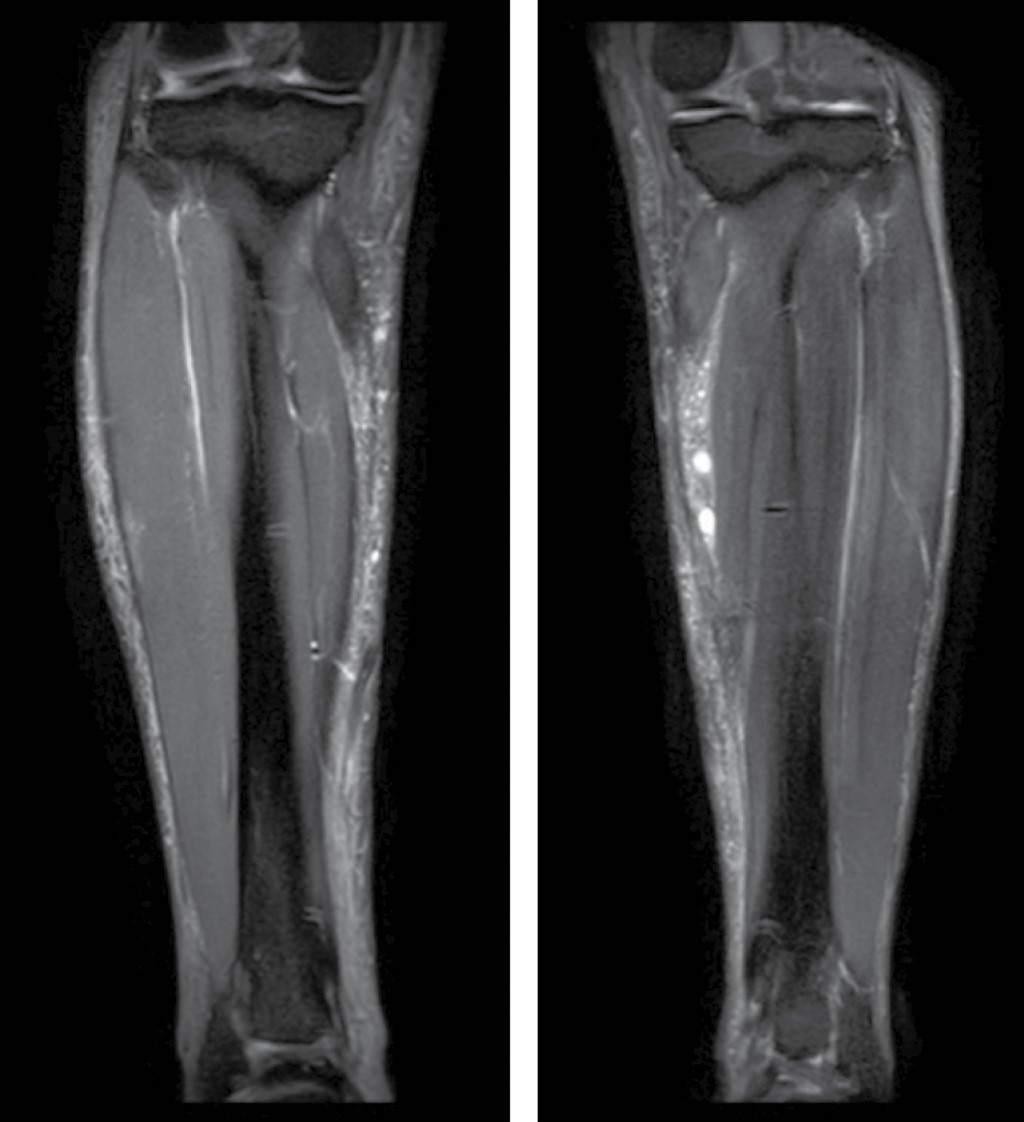

En el estudio de resonancia magnética (RM) de piernas se identificó edema de tejidos blandos superficiales de ambas piernas con depósitos de material modelante en la porción superior del músculo gemelo medial de la pierna derecha y en la pierna izquierda se observa material modelante en toda su longitud sin compromiso de los planos musculares (Figura 3).

Figura 3